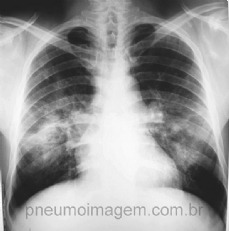

CASO CLÍNICO #26

Paciente com febre, emagrecimento e hemoptoicos. Qual o diagnóstico mais provável? Deixe os seus comentários abaixo. ***** Patient with fever, weight loss and hemoptysis. What is the most probable diagnosis? Write your comments below.